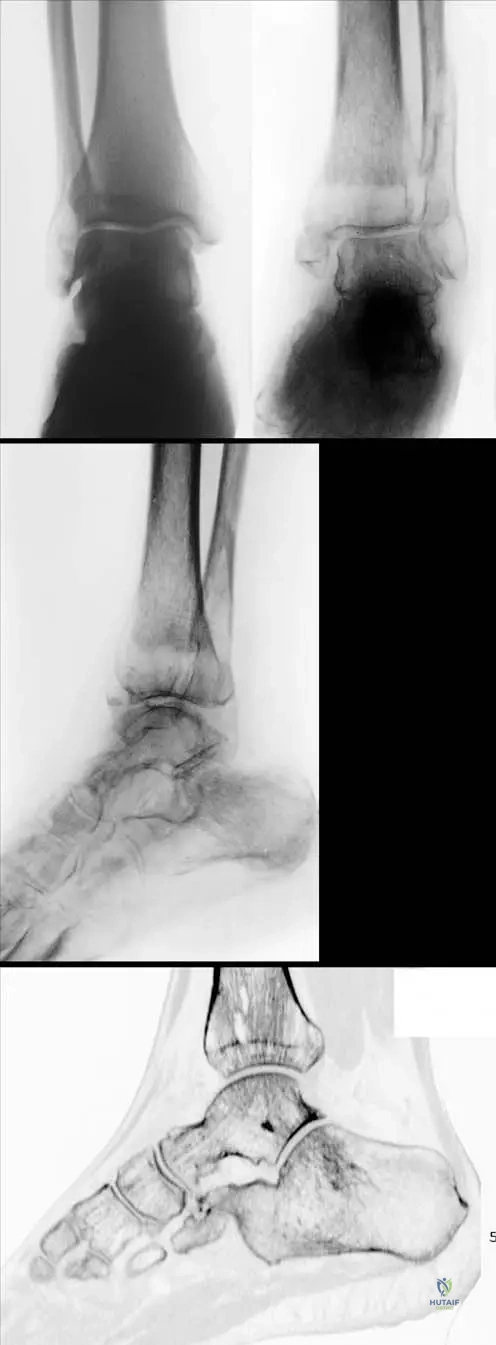

A 60-year-old man with a history of diabetes mellitus presents with a swollen, deformed, and insensate right ankle. He denies any significant trauma. Physical examination reveals a warm, erythematous, and unstable ankle joint with palpable crepitus. Radiographs show severe disorganization of the ankle joint, fragmentation of the talus, and extensive new bone formation.

View Answer & Explanation

Correct Answer: D

Rationale: The combination of a deformed, swollen, unstable, and insensate joint in a patient with diabetes, along with radiographic evidence of severe joint disorganization and new bone formation, is characteristic of Neurogenic Osteoarthropathy, also known as Charcot’s Joint. Diabetes is a common cause. Gout and bacterial arthritis are typically acute and painful. Osteoarthritis is a degenerative process, usually less destructive and not insensate. Reflex sympathetic dystrophy involves pain and autonomic dysfunction, not primary joint destruction.